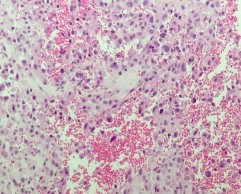

Angiosarcoma: bệnh nhân u mạch máu ác tính duy nhất trong nghiên cứu với tổn thương tại thành trực tràng tiến triển rất nặng với triệu chứng chủ yếu là chảy máu ở hậu môn, vùng mông và tầng sinh môn. Các mảnh cắt vào thành trực tràng phía ngoài lớp cơ và tổ chức xơ mỡ có u, các tế bào u nhân lớn, kiềm tính, không rõ hạt nhân đứng thành đám hoặc đơn lẻ, xen kẽ với các tế bào đại thực bào ăn sắc tố, chảy máu lan tỏa trong mô u, tỷ lệ nhân chia cao, mô đêm tăng sinh mạch mạnh.

Hình 4.7. (A) HE x 100: Các tế bào u dạng biểu mô, xen kẽ là các mạch máu

(B) HE x 400: Rõ hạt nhân, màng nhân méo mó, giàu nhân chia